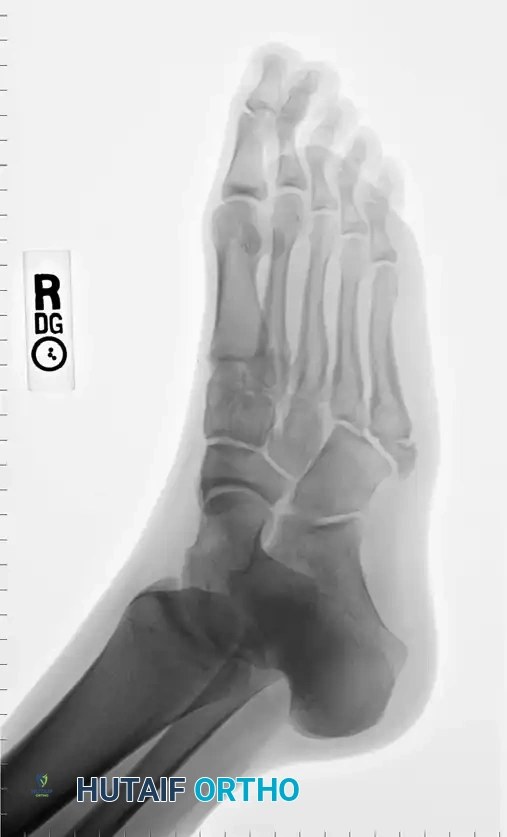

A standard three-view radiographic series of the foot is mandatory for accurate zone classification.

Anteroposterior (AP) radiograph demonstrating the overall alignment and medial cortical integrity of the fifth metatarsal.

Oblique radiograph, which is often the most sensitive view for identifying non-displaced Zone II and Zone III fractures, as it profiles the fourth and fifth intermetatarsal articulation.